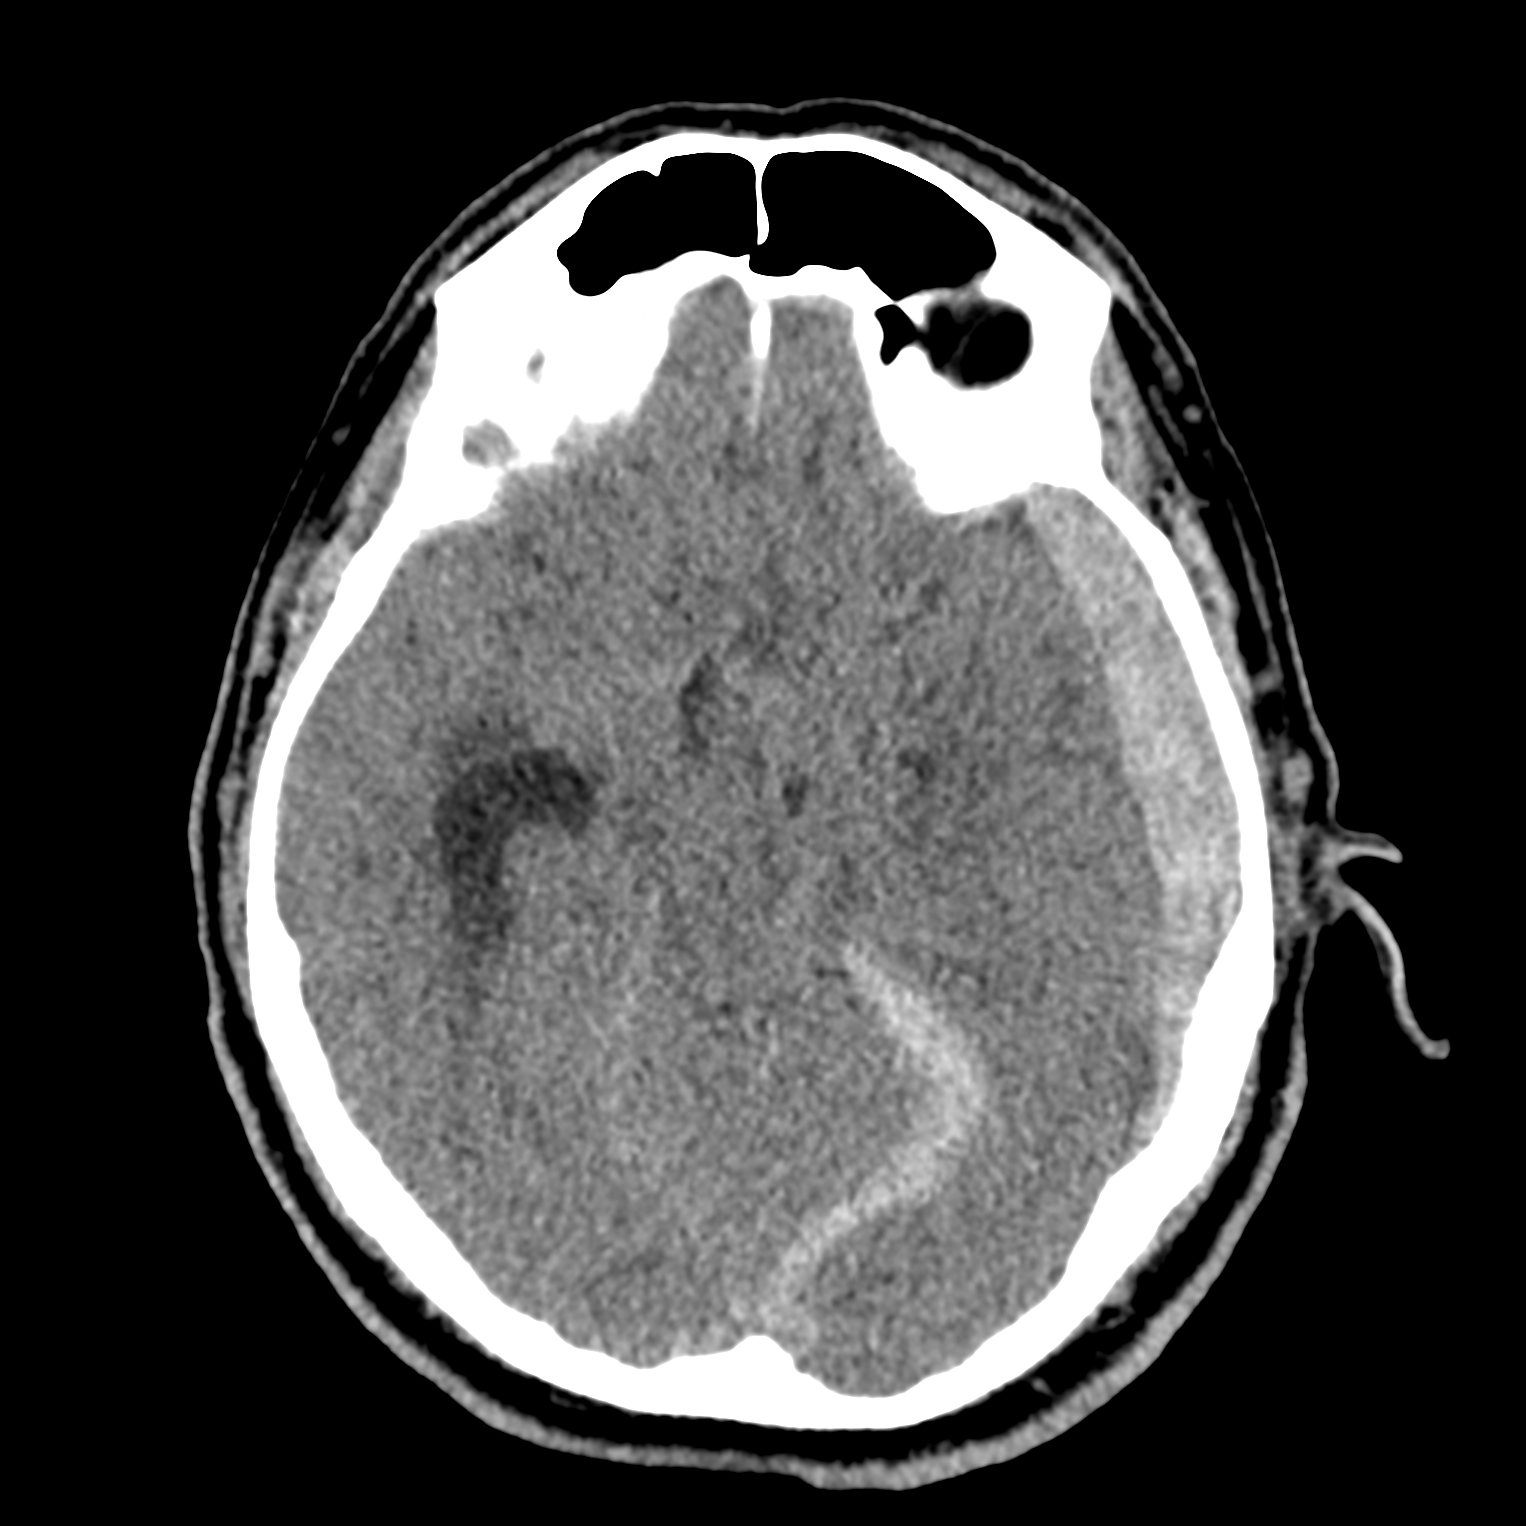

ちなみに画像診断とは、CTやMRIなどの画像を見て、正常か異常か、異常であればそれが何なのかを診断する仕事です。

Case courtesy of Andrew Dixon, Radiopaedia.org. From the case rID: 32383

医療従事者でなければ何のメリットも無いかもしれないのですが、実際の画像を自分でスクロールしながら学ぶことができるというのは、ものすごく大きなことだと思います。

さらに症例の解説を付け加えたら、読影能力アップのための強力なツールになるのではないかと期待しています。